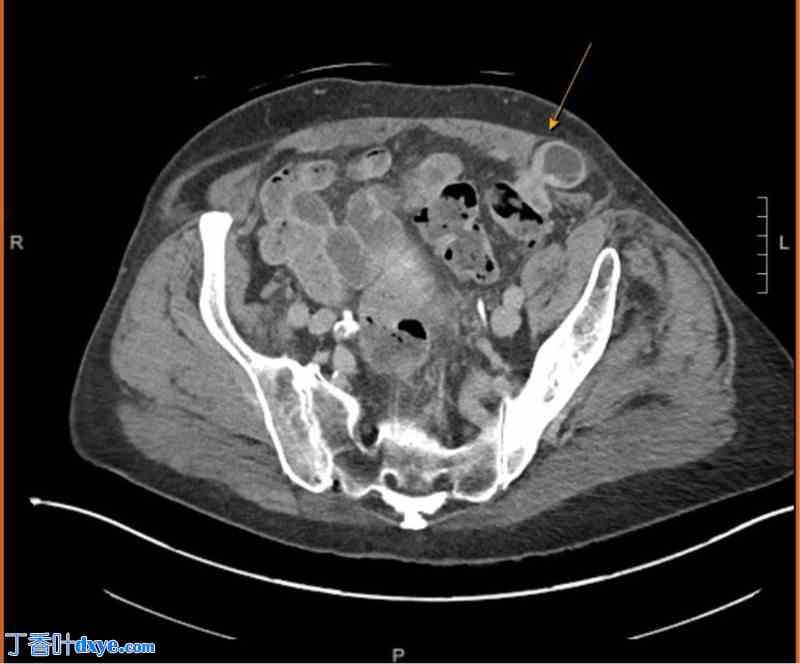

一位60岁男性因左下腹疼痛就诊。患者既往有腹腔镜阑尾切除术史,术中发现明显的双侧盆腔炎症/粘连。检查时,外科医生在左下腹旧5mm套管针穿刺点附近触及一隆起,易于复位。诊断考虑为Spigelian疝或套管针穿刺点疝,建议行开放手术。在全身麻醉下,于术前标记的隆起处做左下腹切口。观察腹直肌筋膜和腹外斜肌筋膜,未发现疝缺损。外科医生未进行修补,直接缝合切口。三周后,患者因肠梗阻入院。CT扫描(图2)显示腹外斜肌筋膜下方、腹直肌外侧存在Spigelian疝。患者经左下腹切口再次探查,切开腹外斜肌筋膜后发现嵌顿的斯皮格尔疝。嵌顿的肠管复位后,疝缺损处进行了直接缝合。

图2

箭头指向左侧斯皮格尔疝,可见一段肠袢嵌顿。